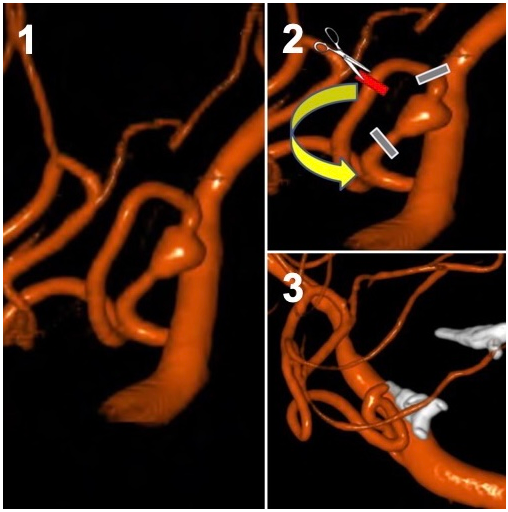

Artery occlusion and bypass is a two-part procedure that combines closure (trap) of a diseased portion of the vessel and bypass which creates blood flow beyond the occlusion point.

Bypass is an open microsurgical technique where a donor vessel is detached at one point in its natural location and rerouted into a position beyond the aneurysm. It is then reattached to the parent vessel to ensure that blood continues flowing.

After the blood flow rerouting strategy has been made (bypass)the diseased portion of the blood vessel containing the aneurysm can be occluded with either trapping with clips or endovascular coils.

Figure 7. Trap and bypass of a ruptured dissecting Posterior Inferior Cerebellar Artery (PICA) aneurysm. 1. Lateral view of the dissecting aneurysm (arrow). 2. Demonstration of the planned clip locations (grey bars) to trap the aneurysm and the cut (red bar) with the proposed reconnection (bypass) to reconnect the artery to the blood flow and prevent a stroke. 3. After the trapping (white clips) and bypass there is preserved blood vessel flow and the aneurysm is trapped between the clips and is no longer at risk of rupture.